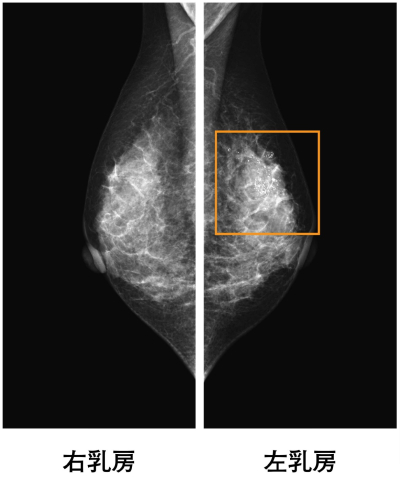

61 歳の女性。乳がん検診のマンモグラフィで異常を指摘されたため来院した。左右の乳房に腫瘤を触知しない。乳房超音波検査で不整形、境界不明瞭で内部に点状の高エコースポットを伴う低エコー領域を認める。マンモグラムを別に示す。